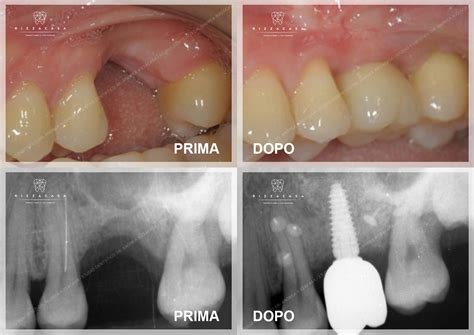

Il 3D-MESH è un dispositivo medico impiantabile, realizzato su misura per il singolo paziente in conformità alla direttiva 93/42/CEE e successive modifiche. Viene utilizzato dai medici dentisti nella pratica chirurgica di rigenerazione ossea, specialmente nei casi di edentulia dove manca una quantità sufficiente di osso autologo.

Lo scopo primario della griglia per rigenerazione ossea è quello di contenere il materiale rigenerativo all'interno della cavità del difetto osseo, guidando il rimodellamento verso una morfologia e un volume definiti. Inoltre, il dispositivo separa efficacemente il tessuto osseo da quello molle, proteggendo il biomateriale inserito e promuovendo la rigenerazione ossea.